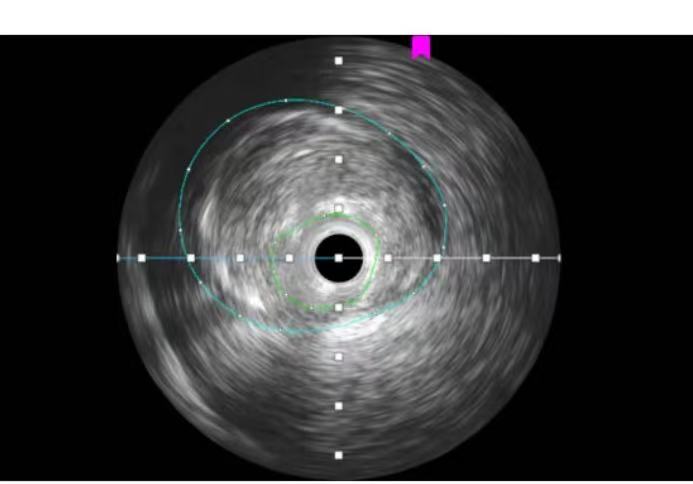

启用血管内超声(IVUS)进行精准探查

近日,周口人合医院胸痛中心成功救治一名急性胸痛患者。入院后冠脉造影初步判断狭窄“不太严重”,但团队凭借经验和临床表现,立即启用血管内超声(IVUS)再精准探查,结果发现一处实际狭窄高达87%的“隐形炸弹”,风险极高。